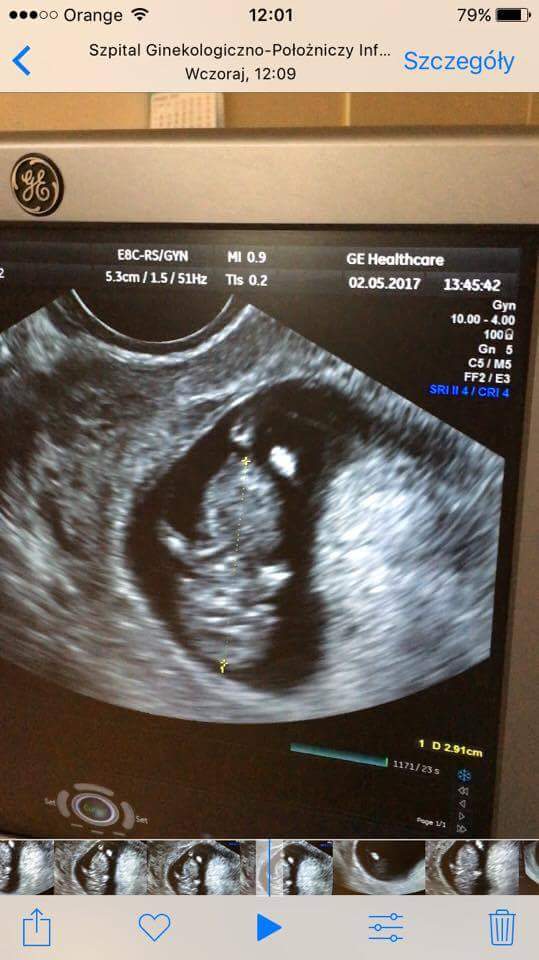

Dziewczyny dzisiaj mam 10 tydzień 0 dni. Wczoraj oglądałam filmik z usg, który nagrał mój mąż i pokazane jest jak doktor mierzy dzidziusia i wychodzi 2.91 cm. Nie za mało?

Mój dzidziol jest niemal identyczny. Tylko parę milimetrów różnicy. Też 10t0d i 3,2 cm. Wszystko zależy jak akurat lekarz zatrzyma obraz usg. Dlatego wahania kilku milimetrów /terminu porodu są plus minus 2 dni na tym etapie

Dodam tylko, że 2 tyg temu na badaniu usg najpierw gin wyliczył mi 7t3d,po czym mówi, że udało mu się lepiej złapać dziecko i już data się zmieniła 7t5d..i to są te różnice kilku milimetrów właśnie. Mogłybyśmy się martwić gdyby jedno dziecko miało 1cm, a drugie 5 cm w tym samym czasie ;)